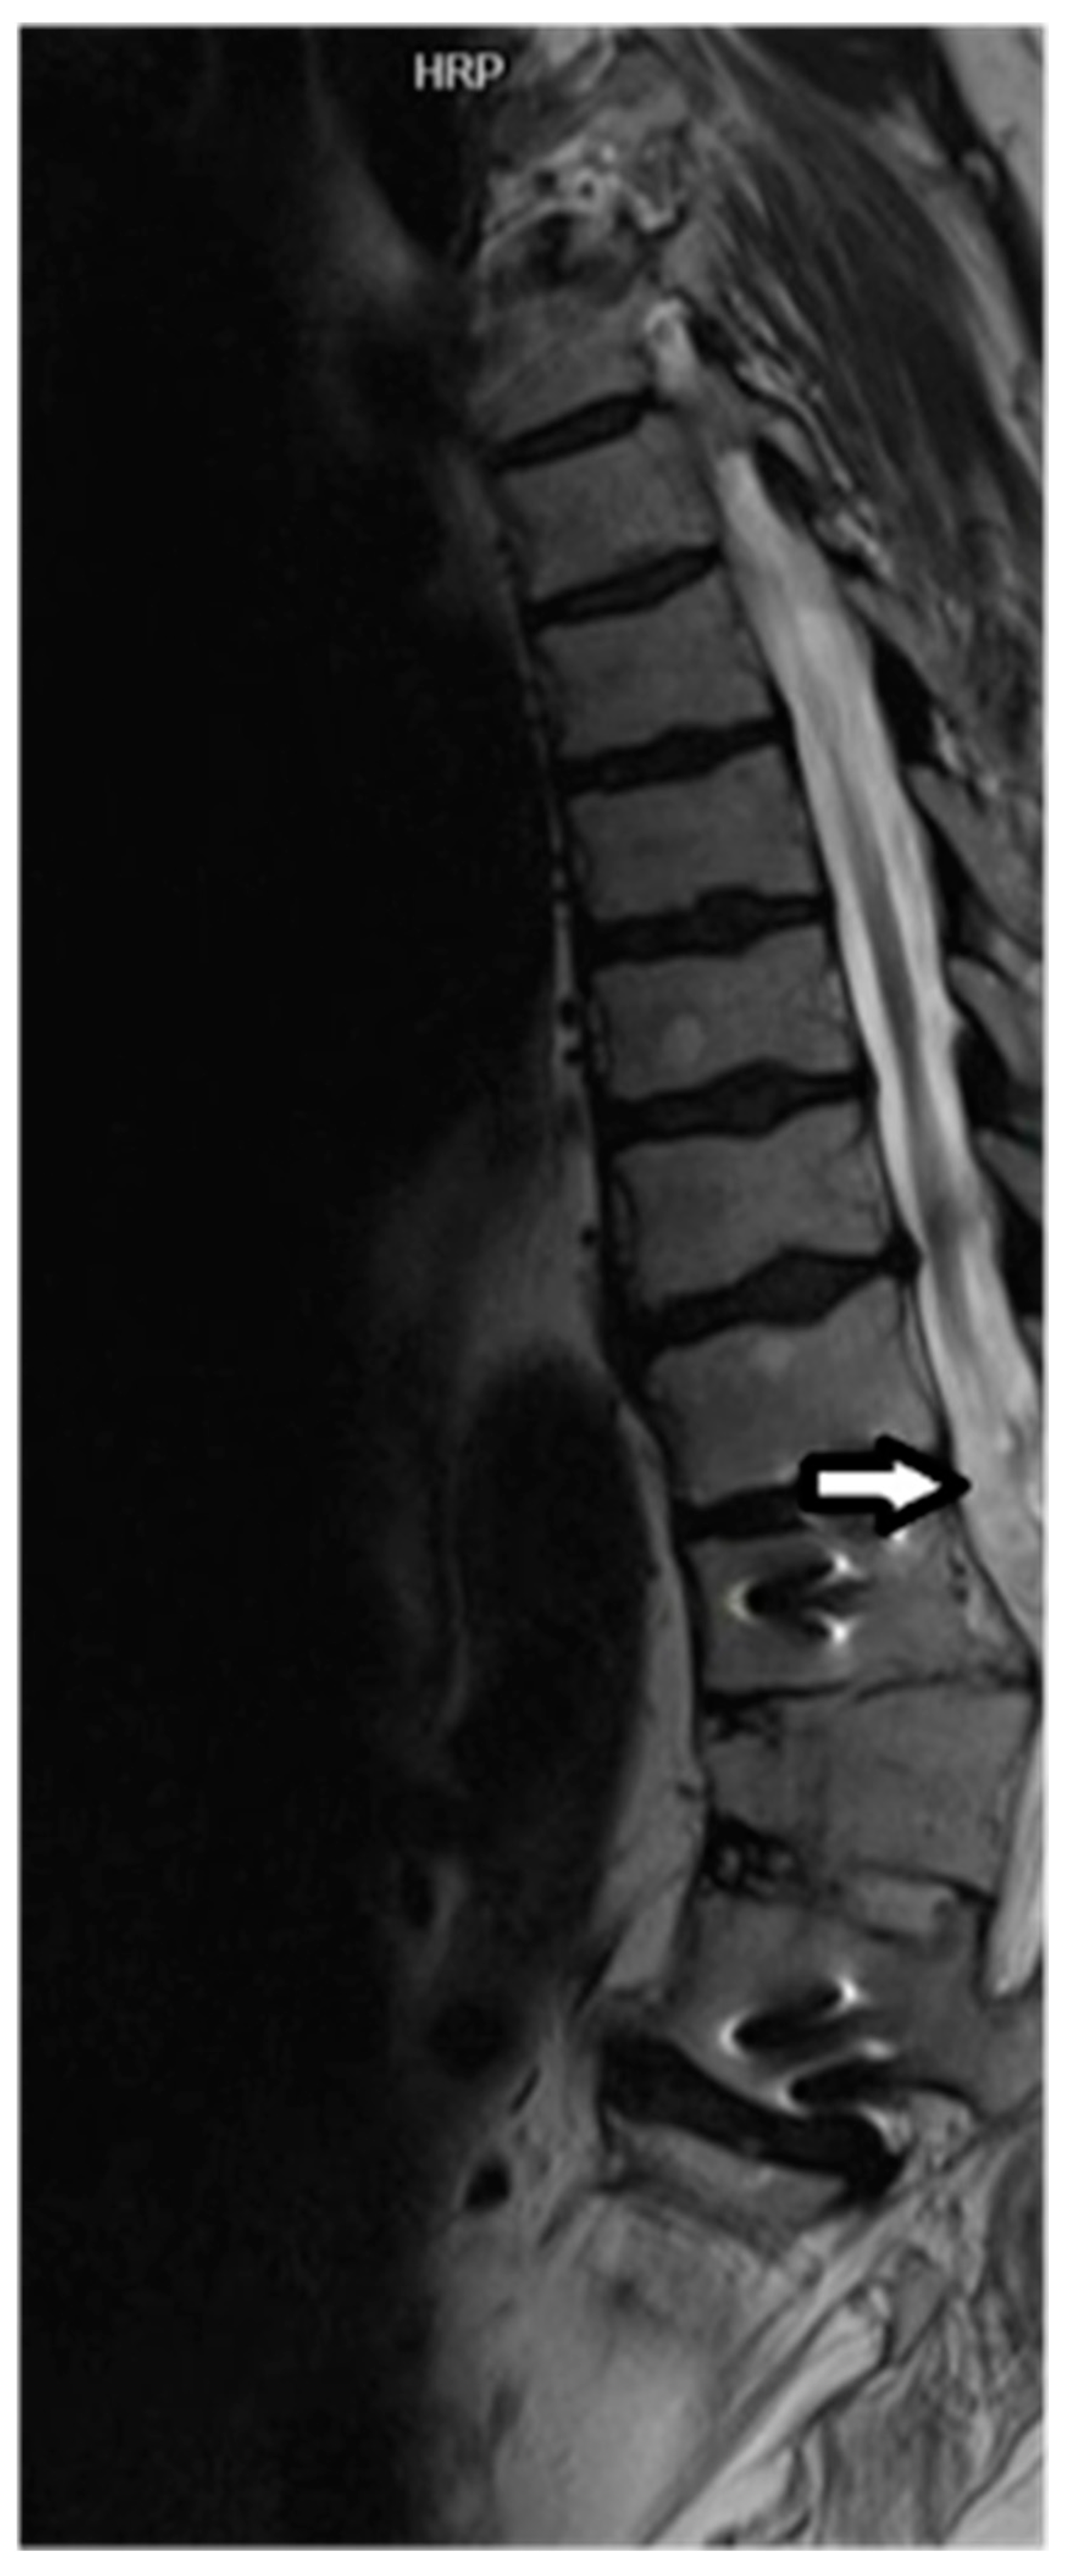

3.2. Promise and Challenges of MRI Tractography